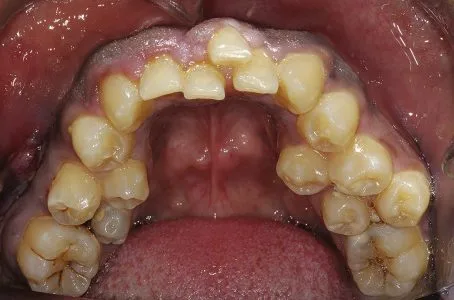

Hyperdontia is the condition of having supernumerary teeth, or teeth that appear in addition to the regular number of teeth. They can appear in any area of the dental arch and can affect any dental organ.The prevalence of hyperdontia is between 1% and 4% of the population with a male to female ratio of 2:1; the majority of cases are limited to a single tooth. There have been reported cases of over 30 supernumerary teeth in one person, but such large numbers are rare.

The main symptom of hyperdontia that you will notice is extra teeth that grow directly behind or close to your usual primary or permanent teeth. These teeth usually appear in adults. They’re twice as common in men than they are in women.

Extra teeth are categorized based on their shape or location in the mouth.